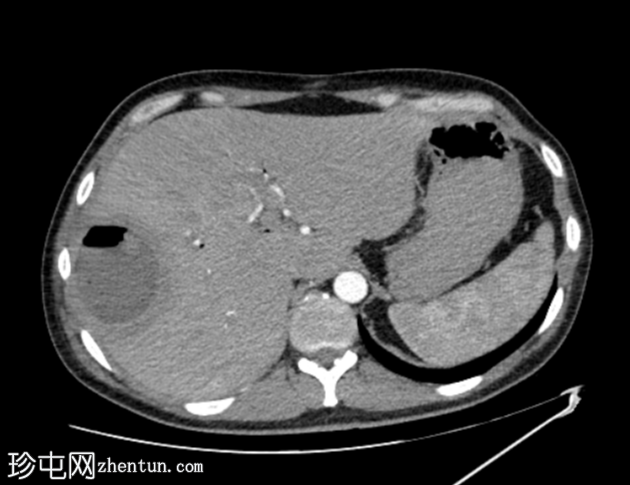

定位扫描

轴位

平扫图像显示胆囊切除夹、胆道积气、胆总管支架及右肝叶VIII段囊性病变伴气液平面。

增强扫描图像显示囊肿边缘强化,周围可见晕环,呈双靶征。